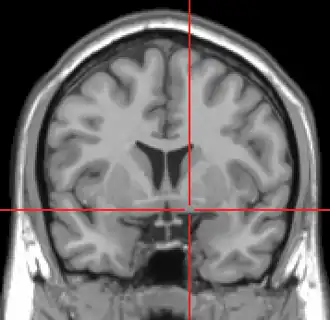

MRI showing a coronal plane of the head with marks showing the location of the substantia innominata, the region in which the nucleus basalis is found. | |